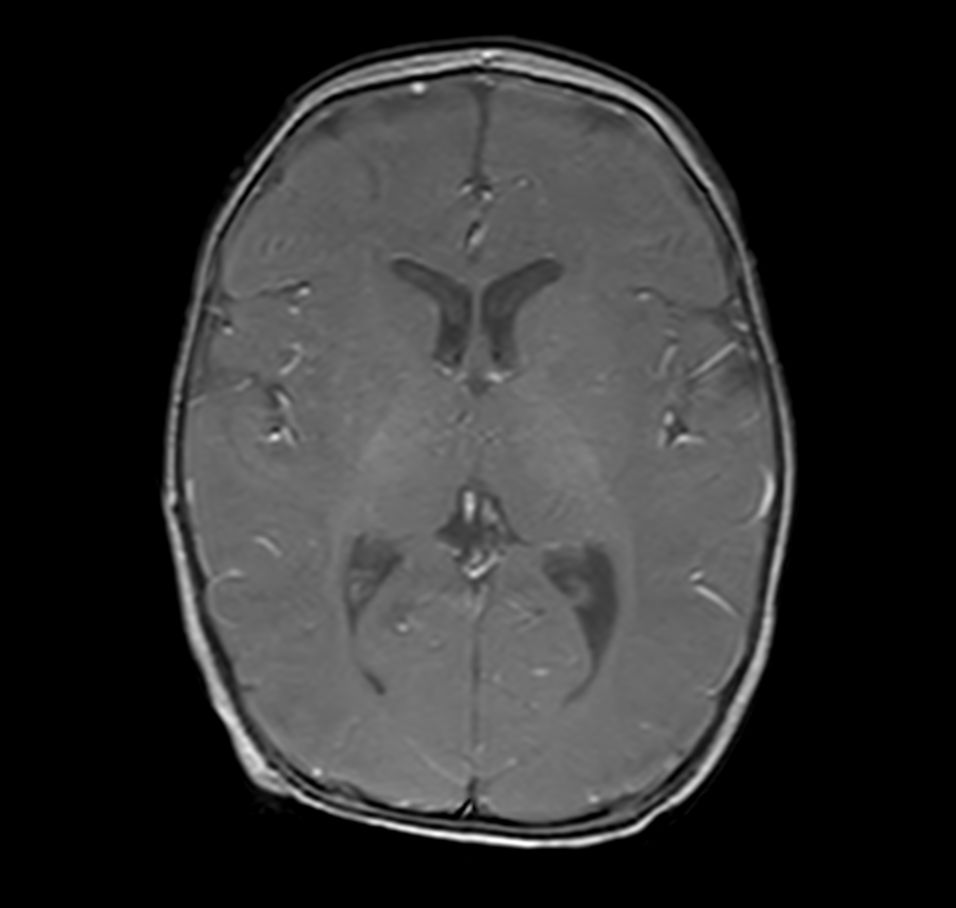

3D T1w TFE with ComforTone - Axial reformat (post-gado)

Axial T1w FFE (post-gado)